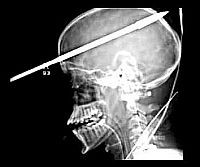

Szigony fúrta át az agyát, de beszélgetett a mentőkkel... Méteres szigonnyal lőtték át egy 16 éves fiú fejét az Egyesült Államokban, ám a gyerek még az eszméletét sem vesztette el, és beszélgetett a mentőkkel.

A baleset Floridában történt. A fiú egy barátjával tavi halászatra indult, amikor a szigonyvetőt a barát véletlenül "elsütötte", az acéllövedék pedig hatalmas erővel Yasser Lopez fejébe csapódott. A szigony 5 centiméterrel a jobb szeme fölött hatolt a koponyába és teljesen átfúrta. A lövés olyan erős volt, hogy a fiút a tóba döntötte, ennek ellenére a gyerek magánál volt, amikor megérkeztek a mentők és - értelmesen - beszélt velük.

Légi úton vitték kórházba, ahol le kellett fűrészelni a szigony szárából, hogy a fiú beférjen a röntgenbe. Bár a lándzsa átfúrta a jobb agyféltekéjét, szerencséjére egyetlen nagyobb eret sem sértett meg. Az orvosok 3 órás műtéttel távolították el a szigonyt.